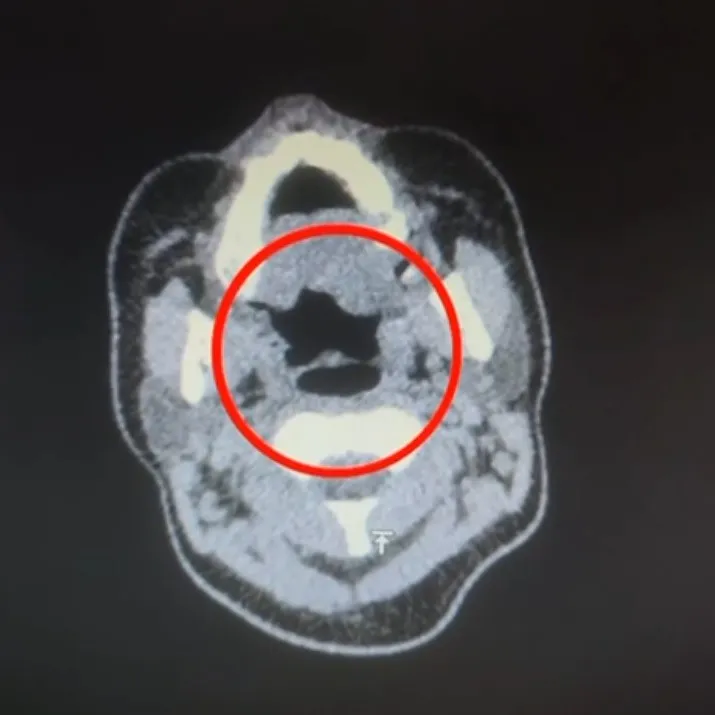

Kayseri'de uluslararası uyuşturucu madde ticareti yapan kuryenin midesinde 50 adet kapsül şeklinde 500 gram uyuşturucu madde ele geçirildi.

Kayseri İl Emniyet Müdürlüğü Narkotik Suçlarla Mücadele Şube Müdürlüğü ekipleri, uluslararası uyuşturucu madde ticareti yapan kurye şahıslara yönelik operasyon düzenledi. Operasyonda A.R.'yi (27) gözaltına alan ekipler, şahsı hastane muayenesine götürdü. Şüphelinin yapılan iç beden muayenesinde, mide kısmında bulunduğu tespit edilen 50 adet kapsül şeklinde toplam 500 gram uyuşturucu madde ele geçirildi.